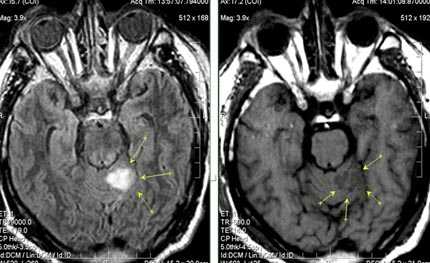

Бассейн кровоснабжения левой верхней мозжечковой артерии, острая стадия НМК.

Зона подострого ишемического НМК, в бассейне правой средней мозговой артерии. В режиме Т1 визуализируется симтом «вуалирования»- изоинтенсивность МР-сигнала.

Одно из преимуществ МРТ в оценке последствий инсульта - возможность визуализировать нисходящую Валлеровскую дегенерацию аксонов в стволе мозга и кортико-спинальном тракте на стороне поражения.